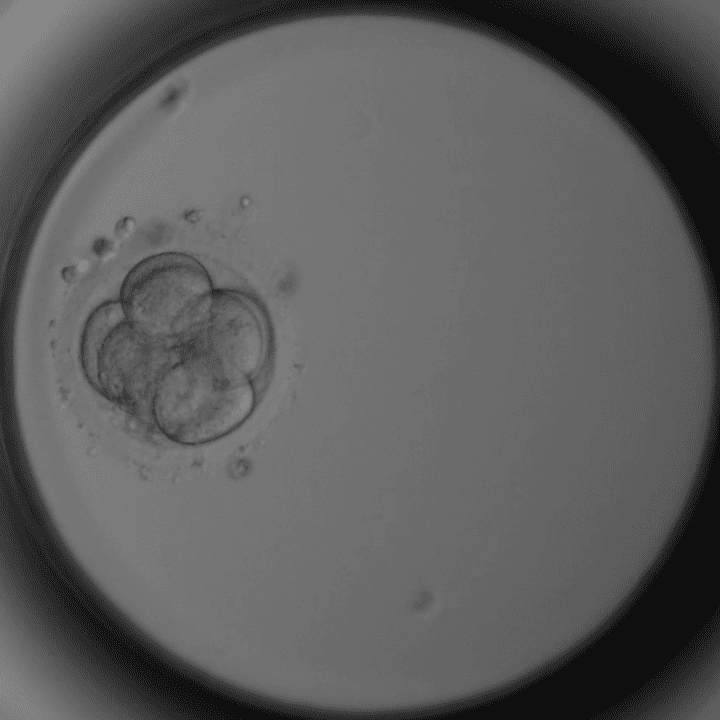

Tag 2 – 4 Zellen

Gleichmäßige Zellen – gutes Zeichen.

Tag 3 – 8 Zellen

Kompaktierung beginnt.

Mikroskopaufnahmen aus unserem Embryologie-Labor in Thalheim bei Wels (Timelapse-Inkubator).

Nur die besten Embryonen werden transferiert oder eingefroren. Manche Embryonen entwickeln sich nicht weiter – das ist biologisch normal.

Dieser Artikel wurde von Dr. Roman Pavlik, Facharzt für Gynäkologie und Reproduktionsmedizin und ärztlicher Leiter der Kinderwunschklinik Dr. Pavlik in Thalheim bei Wels, verfasst. Die Embryo-Mikroskopbilder stammen aus unserem eigenen Labor – sie zeigen echte Entwicklungsstadien aus der täglichen Arbeit unseres Embryologie-Teams.